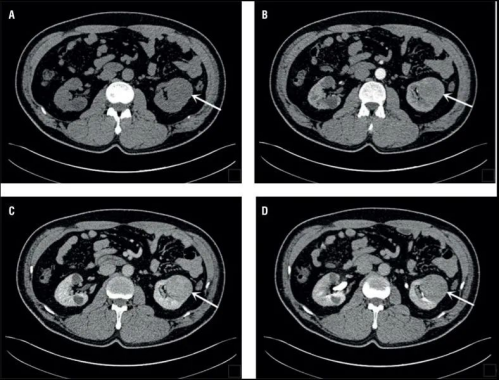

CT

原理簡介:CT檢查相當(dāng)于把人體切成一定間距的小段,間距可以是0.25cm、0.5cm、1cm等等,切完以后可以在圖像上看到每一段橫切面的狀態(tài)。不同的切面呈現(xiàn)不一樣的臟器,通過掃描把人體各個部位的器官和結(jié)構(gòu)拉開,使我們可以看得非常清晰。

應(yīng)用:擅長神經(jīng)系統(tǒng)、心臟大血管疾病

優(yōu)點:可以斷層看,經(jīng)后期處理可以顯示更多信息;

缺點:輻射劑量高;

CT圖像舉例